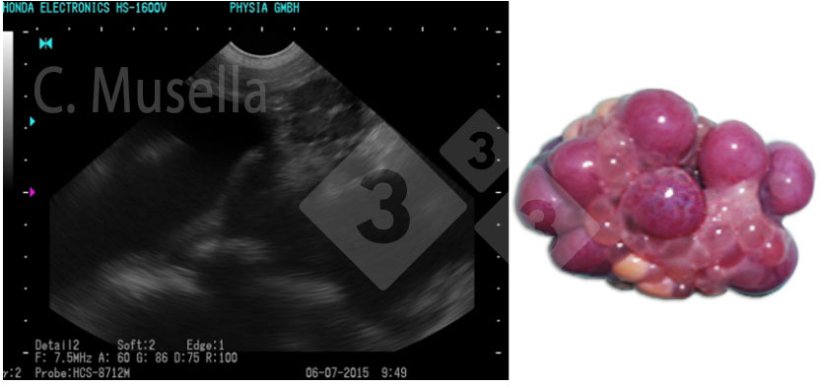

La diagnosi di cisti ovariche singole o multiple è relativamente semplice, sebbene l'identificazione completa del tipo di cisti mediante ecografia non sia sempre certa.